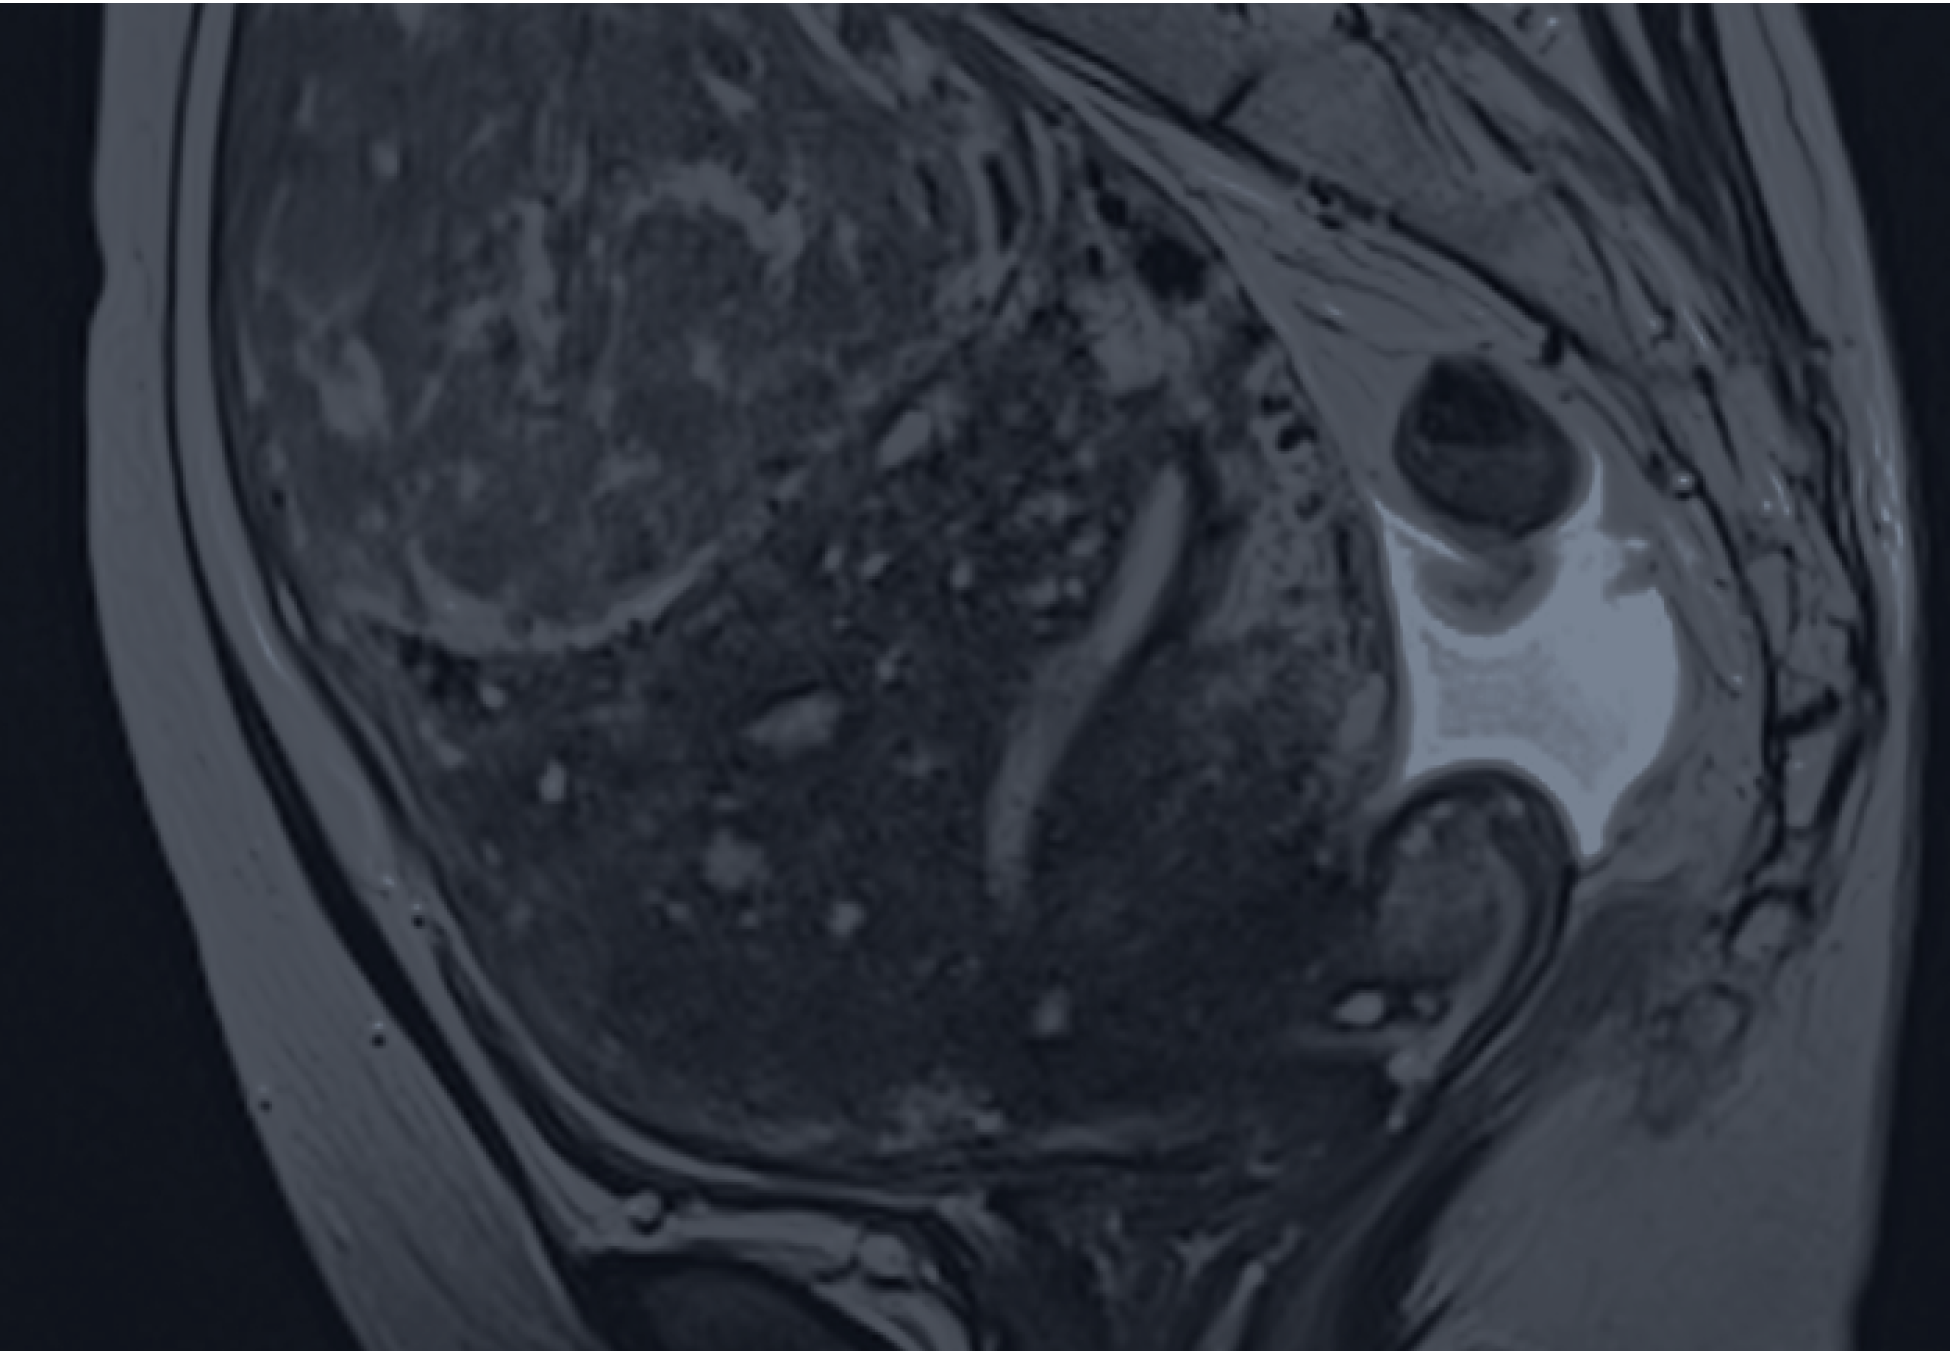

자궁선근종 로얄하이푸

고강도 집속 초음파를 통한 자궁 보존 비수술 치료

- 칼을 대지 않는 무절개·무출혈 치료

- 주변 조직 손상 없는 선택적 병변 파괴

- 당일 입퇴원 및 빠른 일상 생활 복귀